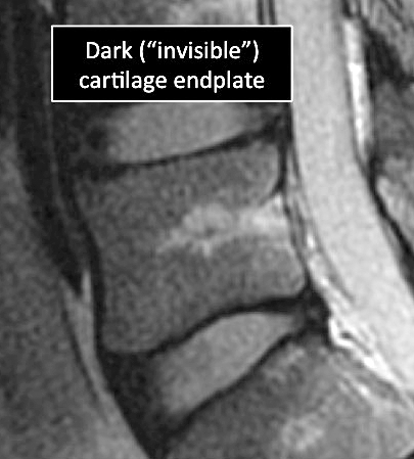

Why Translational MRI of the wrist?

- In the spine, as in many other parts of the body there are certain structures that can’t be seen (they look black or dark) with the standard MRI.

- There are new “software” programs that allow us to see structures with different contrast (bright versus dark).

- Some of these “invisible” or dark structures are unique to the spine (vertebral endplate) and others are found in other parts of the body (e.g. ligaments, cortical bone, nerves).

Spine MRI examinations using the standard MRI techniques (top) and translational MRI techniques (bottom).